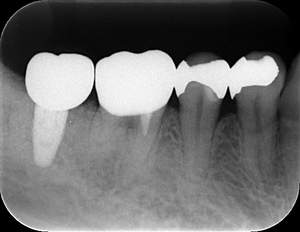

レントゲン写真

- 透過像

| 年齢 | 50代・男性 |

| 主訴 | 右下歯が疼く |

| 治療内容 | ・右下6番インプラント ※1:FGG(遊離歯肉移植術)とは、足りない歯ぐきを上顎から上皮を切り取り移植する外科手術 |

| 治療費 | 合計:902,000円(税込) ■内訳 |

| 治療期間 | 9ヵ月 |

| 治療方針 | 右下の当該歯は歯根破折により保存不可能と診断しました。歯周疾患も伴っていたため抜歯後に骨吸収※1が大きく起こることが予測できました。チタンメッシュ併用骨再生誘導法(GBR※2)を選択しインプラント埋入と同時に行い自然な歯槽骨のラインを再現しました。またGBRを行う際にインプラント辺縁の付着歯肉の減少が起こる為、遊離歯肉移植術(FGG※3)を行い清掃性を考慮した形態に仕上げました。 ■治療方針の解説 治療した右下の歯をレントゲンで撮影したところ根本の部分に黒く写る箇所があり「根尖性慢性周囲炎※1」と診断。また歯周病も進行していました。 ※1 骨吸収・・・歯槽骨という歯を支える骨がなくなっていくこと |

| 担当者所見 | 主訴の右下だけでなく歯茎の腫れ、発赤があり不良補綴や不良充填など他にも治療箇所が多数ありました。プラークコントロールが不良であった為まずはブラッシング指導を行いセルフケアの重要性を理解していただくところからスタートしました。 右下6番の歯はインプラント治療を行なった結果審美的にも機能的にも患者様の満足を得ることができました。骨造成と歯肉移植も行なった為インプラントを支える十分な歯周組織の獲得ができたと思っております。 |